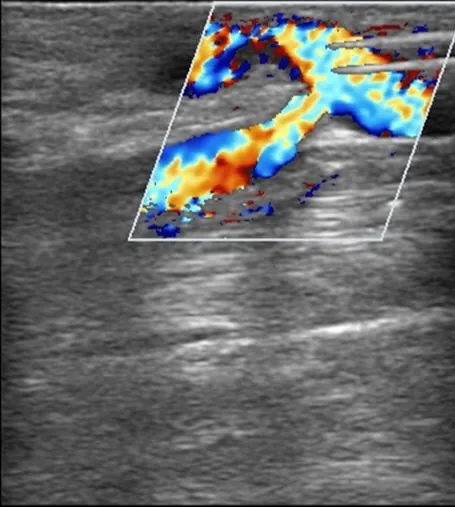

鑒于患者的特殊情況,靳東主任在與團隊充分討論后,決定為其行彩超引導下動靜脈內(nèi)瘺球囊擴張(PTA)+碎栓術,手術成功,秦先生貴要靜脈及頭靜脈處的震顫明顯增強,復測肱動脈流量,達850ml/min。

治療后血流通暢